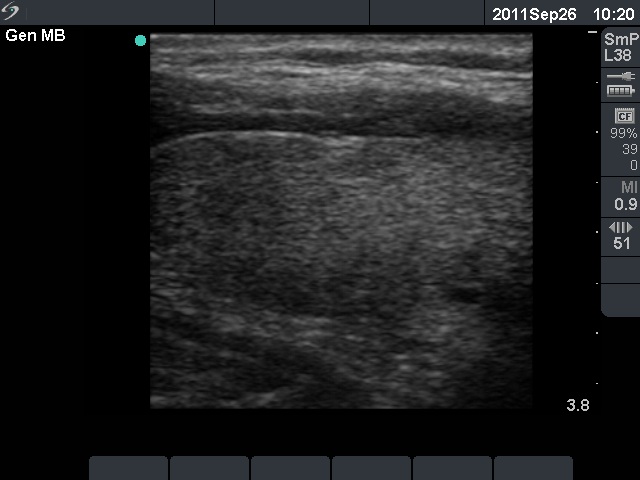

Left lobe, longitudinal scan. Moderately hypoechogenic areas are demonstrated.